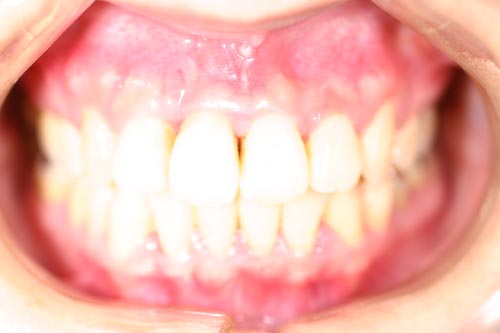

上顎の中央の歯一本が前にとびだしている治療例

Before

上顎の中央の歯一本が前にとびだしている症例です。これだけ前に出ていると、歯を抜いて並べていくか、何本かの歯を削らないときれいに並べられません。

このケースは、上の顎に矯正用のミニスクリュー{矯正用ミニインプラント}を入れて、歯を抜かず、削りもしないで、しかも上顎だけの矯正で治した症例です。

矯正用インプラントを使うことによって歯並び全体を後方に動かすことができるようになったため、このような治療ができるようになりました。

年齢 20代

治療期間 8ヶ月

治療費用 800,000円

治療のリスク 特になし